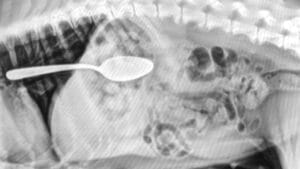

If you suspect your pet has ingested a foreign object, it is essential to contact your veterinarian immediately. Your veterinarian will likely perform a physical examination. Abdominal palpation is a key part of the diagnosis, but advanced diagnostics like abdominal radiographs (X-rays) are often needed to confirm the presence of an obstruction. X-rays may show fluid and gas buildup, which are signs of a foreign body obstruction. If X-rays are inconclusive, an abdominal ultrasound may be used to further investigate the cause of the signs.